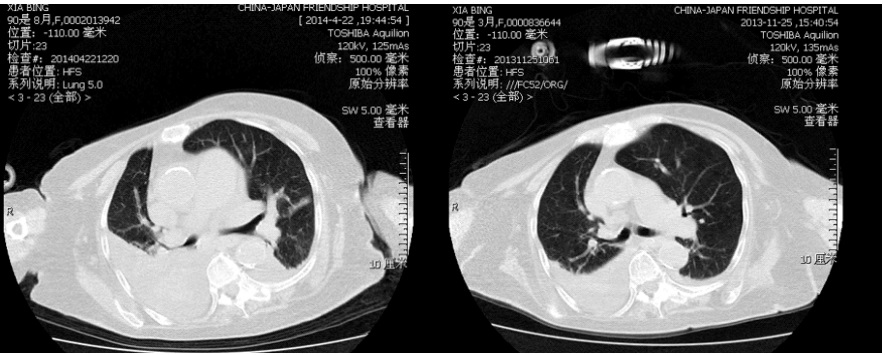

患者女,90岁,因“胸闷、喘憋、精神不振3 d”于入院。既往有慢性阻塞性肺疾病病史。查体:T 36.8℃,P 78 次/min,RR 40 次/min,BP 105/67 mmHg(1 mmHg=0.133 kPa),呈昏睡状态,脊柱后凸侧弯畸形,右肺中下肺野、左下肺野呼吸音低,右上肺野可闻及少量湿啰音,心率78次/min,律齐,未闻及杂音,双下肢无水肿。降钙素原2.0 ng/mL;血气分析:pH 7.14,PaCO2 108 mmHg,PaO2 62 mmHg,SaO2 83%;2014年4月22日与2013年11月25日胸部CT:①双下肺渗出实变影。②左上肺陈旧性病变(图 1)。痰培养:铜绿假单胞菌、嗜麦芽窄食单胞杆菌。给予头孢吡肟抗感染,行有创机械通气,容量控制模式:RR 12次/min,VT 250 mL,PEEP 4 cmH2O(1 cmHg=0.981 kPa),FiO2 60%,监测PaCO2 60 mmHg~70 mmHg,PaO2 65 mmHg~75 mmHg。4月28日行自主呼吸试验(SBT)达标后脱机拔管,鼻导管吸氧2 L/min。5月2日出现痰液粘稠、咳痰无力、嗜睡症状,复查PaCO2 86 mmHg,给予无创呼吸机辅助呼吸,BiPAP模式,IPAP 12 cmH2O,EPAP 5 cmH2O,RR 15次/min,FiO2 35%,监测PaCO2 85 mmHg~90 mmHg,PaO260 mmHg左右。

| 图 1 图 1 左上肺陈旧性病变 |